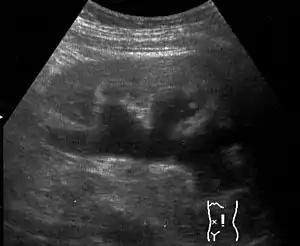

| Renal ultrasonography of hydronephrosis caused by a left ureteral stone.] | |

Imaging studies, such as an intravenous urogram (IVU), renal ultrasonography, CT, or MRI, are also important investigations in determining the presence and/ or cause of hydronephrosis. Whilst ultrasound allows for visualisation of the ureters and kidneys (and determine the presence of hydronephrosis and / or hydroureter), an IVU is useful for assessing the anatomical location of the obstruction. Antegrade or retrograde pyelography will show similar findings to an IVU but offer a therapeutic option as well. Real-time ultrasounds and Doppler ultrasound tests in association with vascular resistance testing helps determine how a given obstruction is effecting urinary functionality in hydronephrotic patients.[10]

Massive hydronephrosis as marked by the arrow.- Renal ultrasonography of hydronephrosis[14]